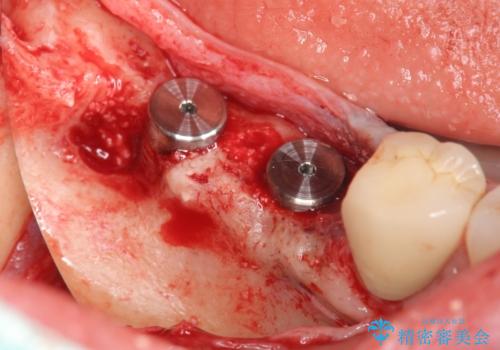

インプラントの埋入には十分な骨量が必要ですが、虫食い状に骨が足りなかった為インプラントの埋入と同時に骨の増成を行いました。

インプラントを埋入する手術と同時に骨の増成を行う場合と、埋入前に骨の造成だけを行う場合があります。